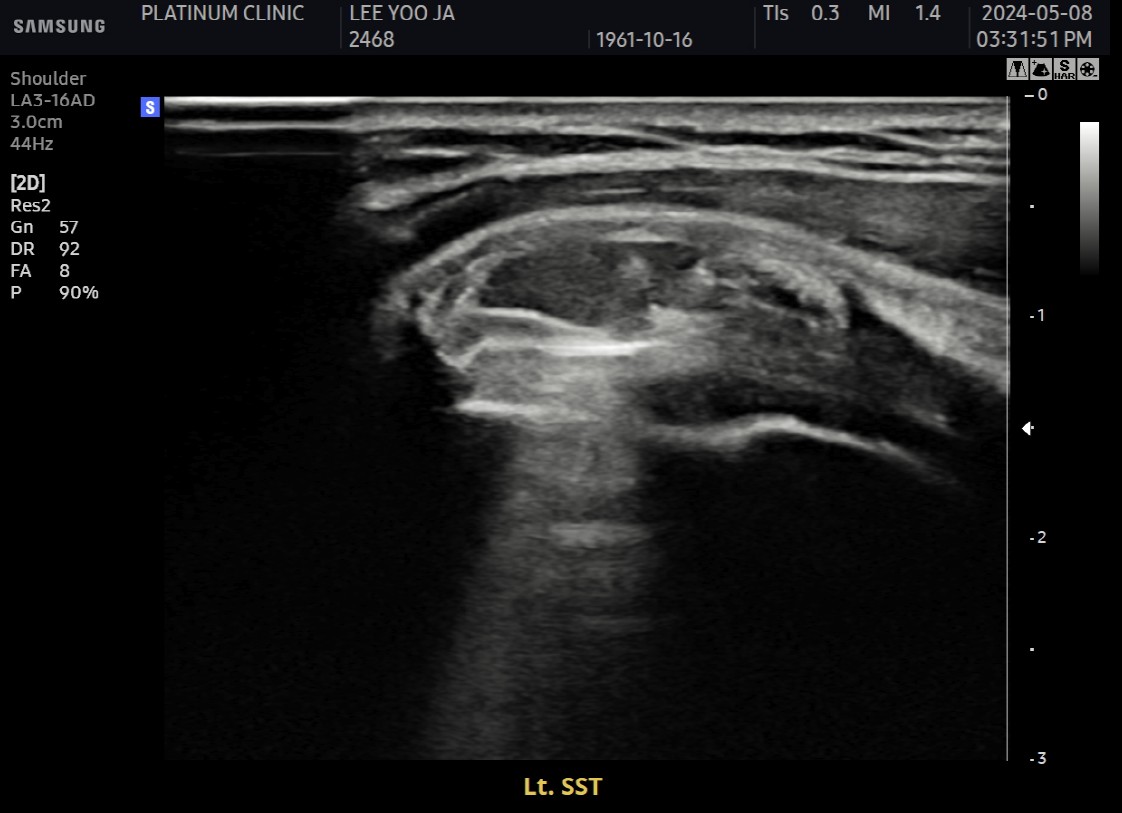

Step 4: 흡입

분쇄된 석회를 강력하게 흡입합니다.

분쇄 조각들이 빨려 나옴

흡입된 석회를 눈으로 확인 가능

큰 조각부터 작은 가루까지 제거

Step 5: 세척

인대 사이사이에 남은 미세 석회를 세척합니다.

생리식염수 주입

인대 조직 사이 잔여 석회 씻어냄

깨끗해질 때까지 반복

Step 6: 최종 확인 및 마무리

초음파와 X-ray로 석회 제거 확인 후 마무리합니다.

초음파: 석회 부위 확인

X-ray: 석회 완전 제거 확인

시술 부위 드레싱

전체 시술 시간은 약 30~40분입니다.